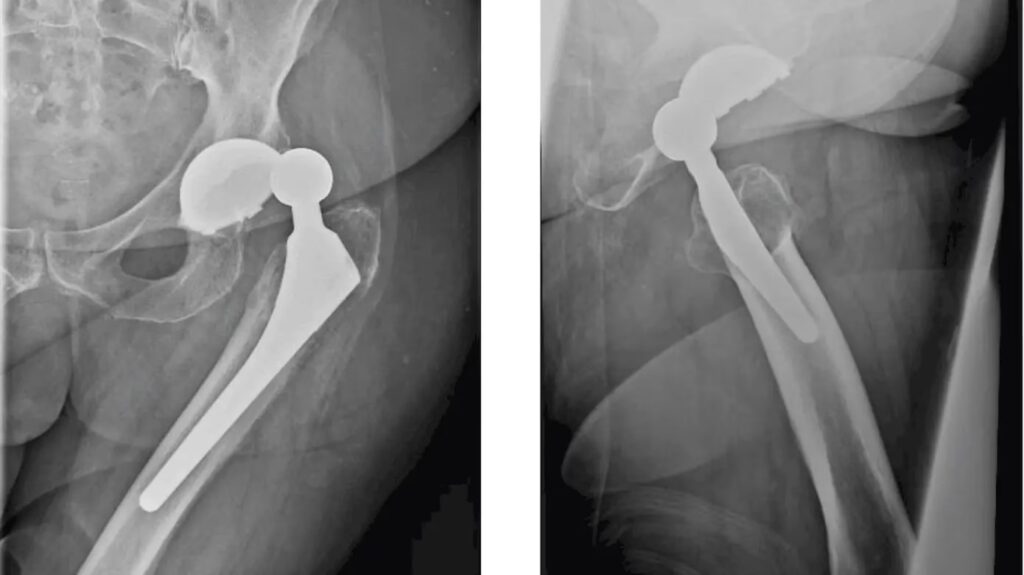

Hvad er en hofteprotese?

En moderne hofteprotese er et teknologisk vidunder designet til at efterligne funktionen af et naturligt hofteled. Den består typisk af to hoveddele: en kugle (caput) og en skål (acetabulum). Disse dele er fremstillet af materialer, der er skabt til at blive accepteret af kroppen, såkaldte biokompatible materialer. Kuglen er ofte lavet af poleret metal (f.eks. en kobolt-krom-legering) eller stærk keramik. Skålen har typisk en ydre skal af metal og en indre 'liner' af slidstærkt plastik (polyethylen), keramik eller metal. Valget af materialer afhænger af patientens alder, aktivitetsniveau og knoglekvalitet. Proteserne er designet til at modstå korrosion og mange års slid.